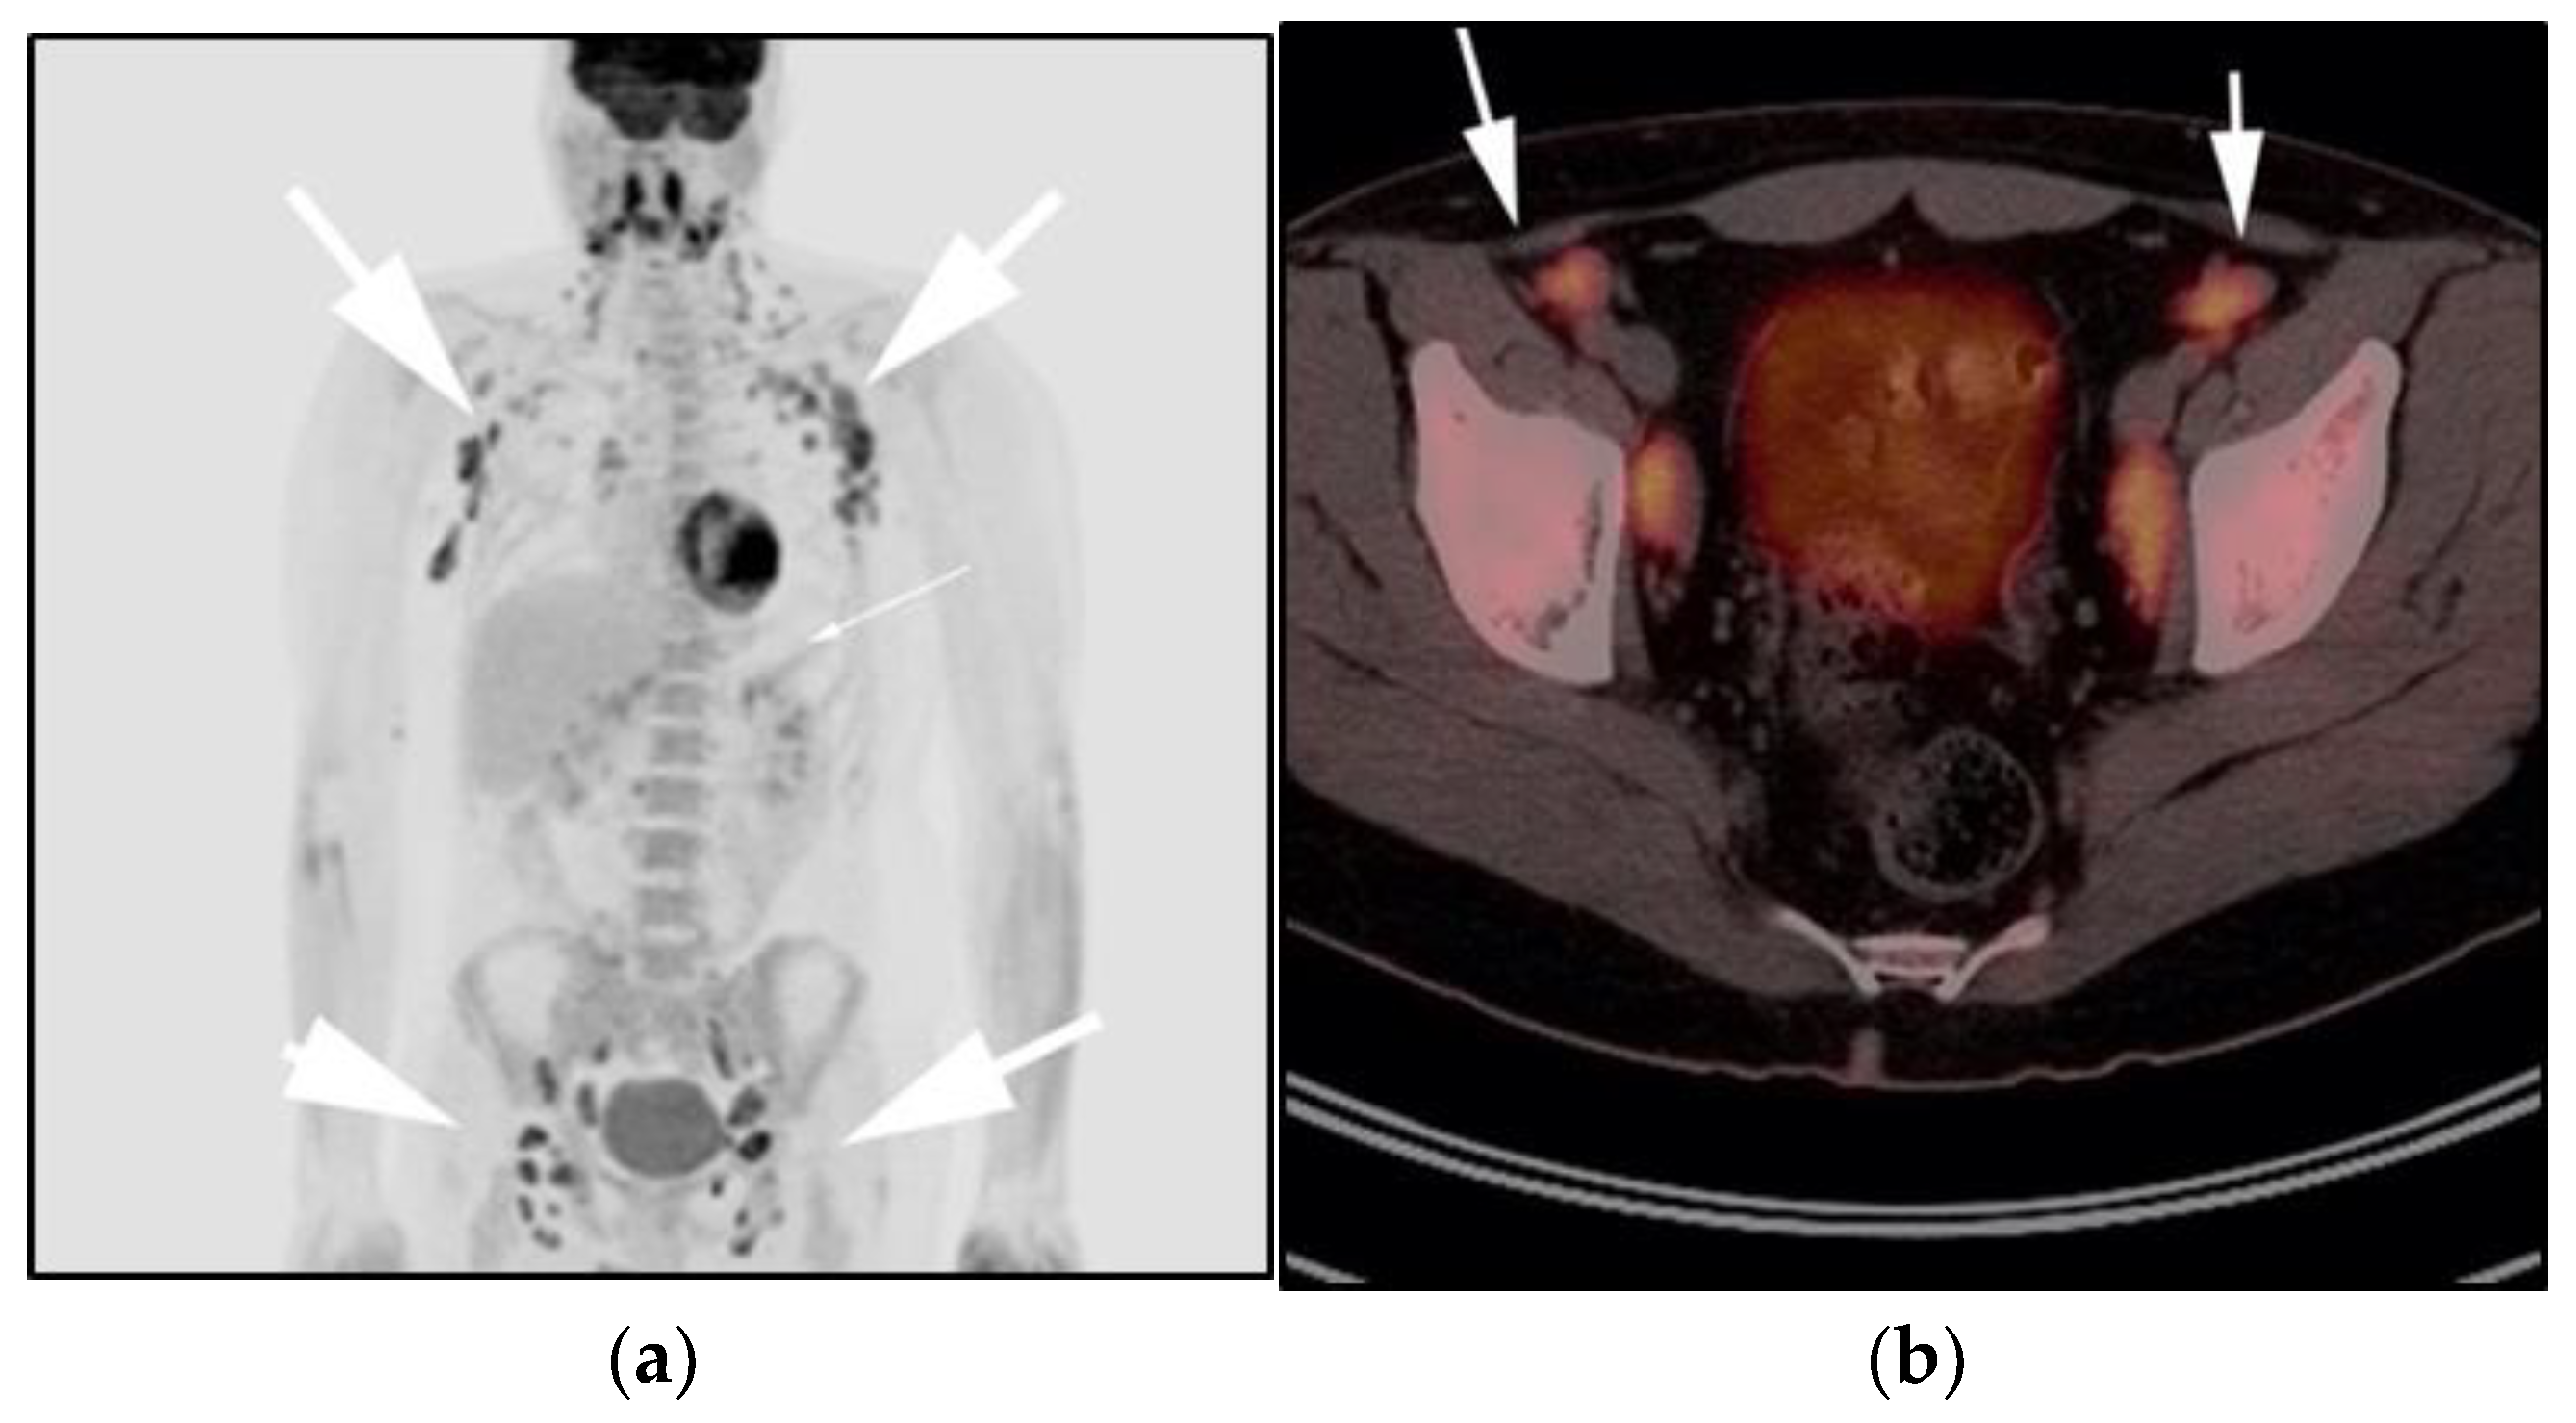

Figure 7.

Imaging in a 20-year-old female with history of classic Hodgkin’s lymphoma (CHL) who had 4 cycles of chemotherapy. (a) Axial 18F-FDG PET/CT showing residual wedge-shaped/triangular activity seen within the anterior mediastinum (arrow). There was concern for residual disease vs. thymic rebound hyperplasia. (b) MRI axial T1 in phase and (c) MRI axial T1 out of phase show intermedial signal on T1 in phase (arrow) with dropped signal on the out of phase sequence (arrow), consistent with fat content due to thymic rebound hyperplasia.

Figure 8.

Imaging in a 60-year-old female presenting with ill-defined anterior mediastinal mass. (a) Axial 18F-FDG PET/CT showing ill-defined hypermetabolic mass within the anterior mediastinum (arrow). This was biopsy-proven thymic carcinoma. (b) MRI T1 in phase sequence, (c) MRI T1 out of phase—note there is no dropped signal on the T1 out of phase (arrows) due to lack of fat. This is consistent with residual disease.

The use of 18F-FDG PET/CT is essential in the evaluation of patients with PMLBCL to reveal sites of disease not visible on CT and to provide more accurate staging and radiation field planning (Figure 6). 18F-FDG PET/CT may also be beneficial for restaging after chemotherapy and/or radiotherapy, or when relapse is suspected [34]. Negative 18F-FDG PET/CT after two or four cycles of chemotherapy has a negative predictive value and may predict excellent outcome in patients, achieving complete response without relapse. Patients who have residual activity equal to or higher than liver activity after immunochemotherapy treatment are more likely to relapse. In such instances, the addition of radiotherapy to the treatment regimen should be considered to avoid relapse in those high-risk patients. Relapse usually occurs within 1 year and is more likely to be widespread, involving distant extranodal sites such as the CNS, liver, kidneys, adrenal glands, GI tract, ovaries, and pancreas. Late relapses are very uncommon [35]. 18F-FDG PET/CT can also efficiently assess post-treatment response, differentiating between necrotic or fibrotic tissue and residual masses containing viable tumor [33,36]. There are various potential challenges to 18F-FDG PET/CT post-treatment implementation, including false-positive results secondary to thymic rebound hyperplasia, specifically seen in the young population. This can be limited by increasing the interval between treatment and imaging. Additionally, MRI can be helpful in those cases, and high signal on T1 in phase imaging with loss of signal on the out of phase sequences is consistent with thymic rebound hyperplasia (Figure 7 and Figure 8) [34,37].